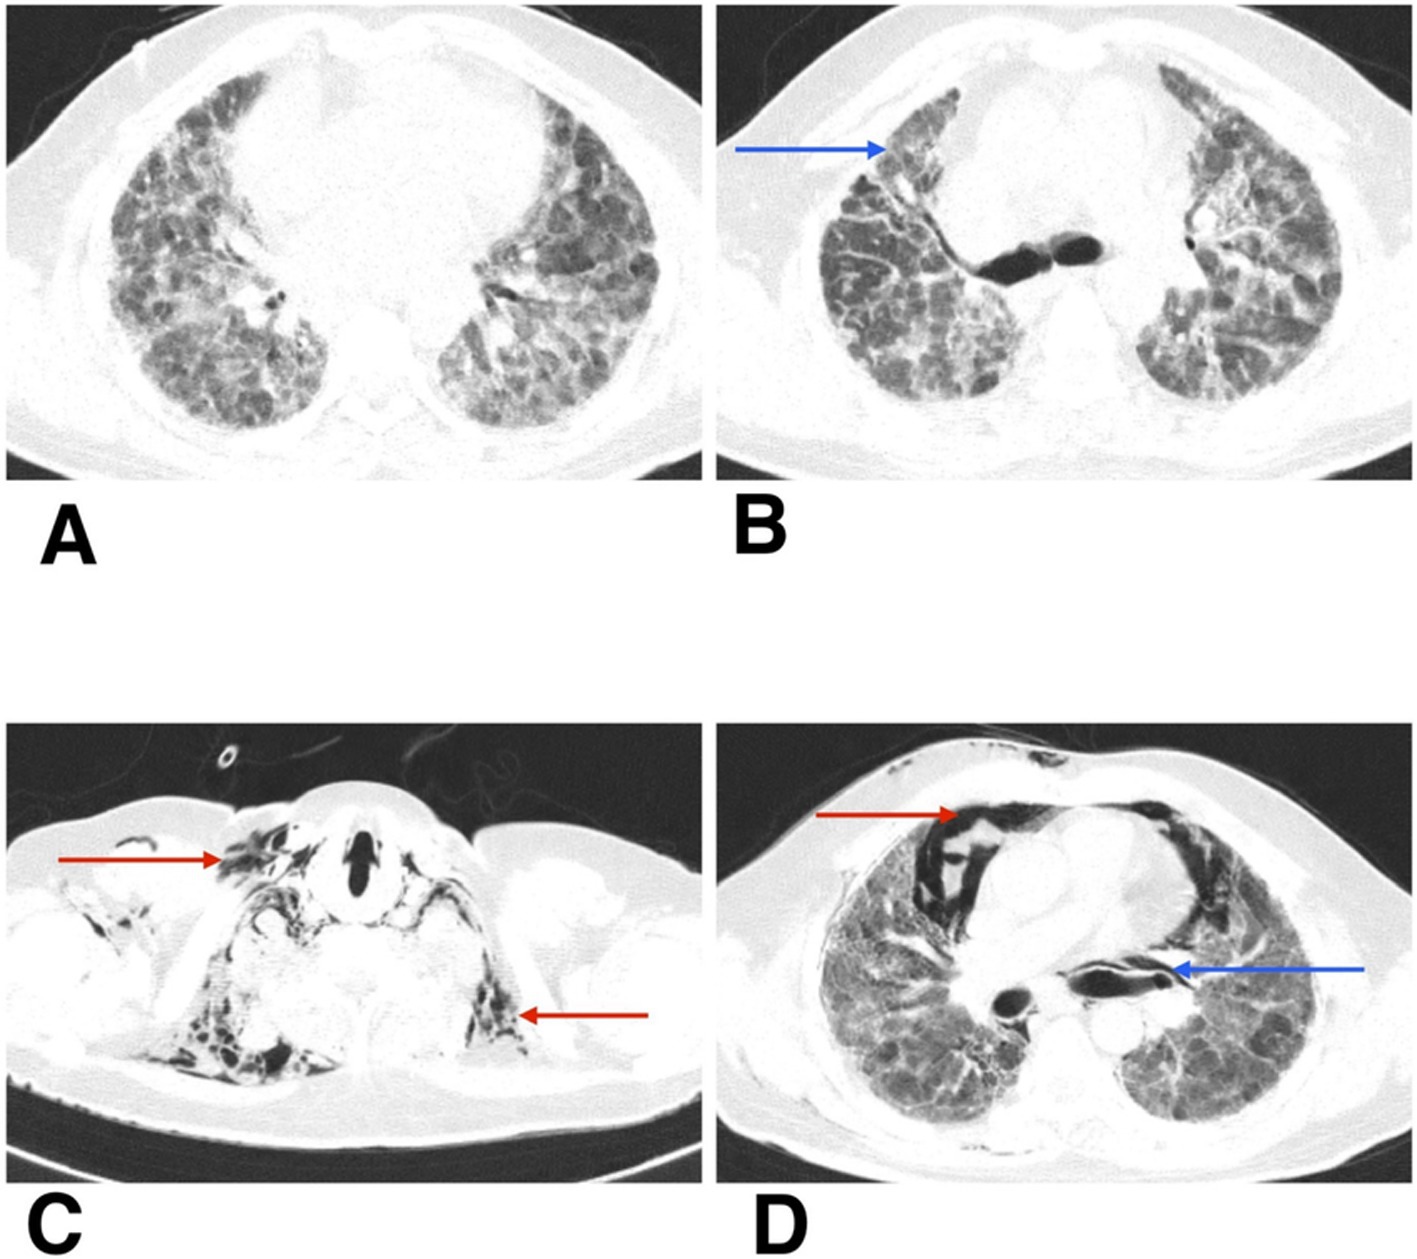

He was admitted to the respiratory medicine department and transferred to the intensive care unit (ICU) for close monitoring. Chest radiography revealed reticular opacities in the bilateral lower lung zones (Figure 1A). High-resolution computed tomography (HRCT) of the thorax revealed findings consistent with fibrotic non-specific interstitial pneumonia (NSIP), including patchy ground-glass opacities, reticulations, and areas of architectural distortion (Figures 2A,B).

Figure 2. (A,B) HRCT thorax of axial section shows patchy ground-glass opacities, reticulations, and areas of architectural distortion (blue arrow). (C,D) HRCT thorax of axial section on follow-up shows subcutaneous emphysema (red arrow), spontaneous pneumothorax (red arrow), and pneumomediastinum (blue arrow).

During his first admission, the patient was managed with oxygen therapy, BiPAP support, and the treatment regimen detailed above. He improved clinically and was discharged with advice for long-term oxygen therapy at home and continuation of prescribed medications. However, after 1 month, he presented again to the emergency department with clinical deterioration. On this second presentation, he developed crepitus over the chest wall and neck, prompting urgent radiological reassessment. A chest X-ray revealed subcutaneous emphysema and features suspicious for pneumomediastinum (Figure 1B). Repeat HRCT thorax confirmed the presence of right-sided spontaneous pneumothorax, pneumomediastinum, and subcutaneous emphysema (Figures 2C,D).

Autopsy and clinicopathological correlation identified the cause of death as acute type I respiratory failure due to fibrotic non-specific interstitial pneumonia (fNSIP), characterized histologically by dense collagenous fibrosis with temporal uniformity, mild chronic inflammation, and relatively preserved alveolar architecture, and complicated by spontaneous pneumothorax, pneumomediastinum, and subcutaneous emphysema (Figures 3A,B).